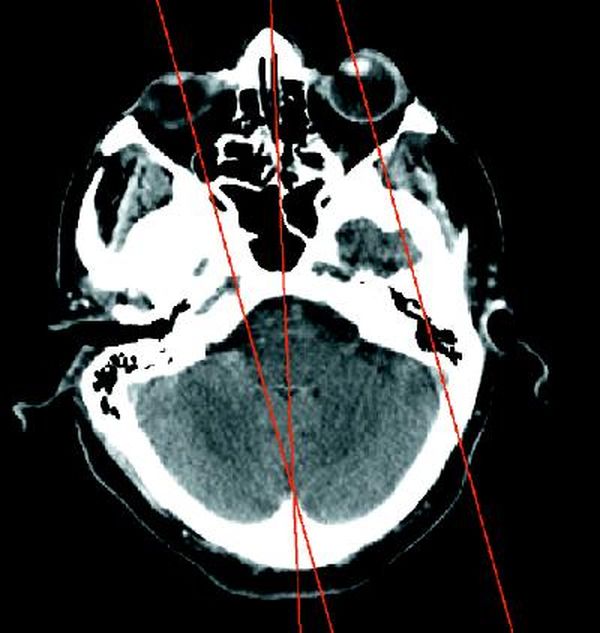

我们的每只眼睛都有6块肌肉控制其不同方向的运动,大脑对这些肌肉的控制使双眼能保持相同的注视方向

约翰斯·霍普金斯大学的眼科学教授大卫·盖顿(David Guyton)说:“首先是有了备用的眼睛,以防发生事故。其次是所谓的深度知觉,这是一种可以帮助我们捕猎的演化特征。”所谓深度知觉,亦称立体知觉或距离直觉,是指人对物体远近距离的直觉。然而,如果两只眼睛不能完美地同步运动,就会导致复视,即把一个物体看成两个物体的视功能障碍。那么,身体是如何确保我们的双眼总是一起转动的呢?大脑利用一个反馈系统来精细地调整控制眼睛的肌肉长度,从而防止复视。盖顿表示,这一系统能产生非常精确的眼球运动。根据《加拿大医学协会杂志》(Canadian Medical Association Journal)2005年的一篇评论,我们的每只眼睛都有6块肌肉控制其不同方向的运动,而且两只眼睛的每一块肌肉都必须同时被触发,才能协调一致地运动。“你可以想象一下,这真的非常令人惊奇,”盖顿说,“大脑具有一个组织非常良好的神经系统。随着时间的推移,大脑学会了应该对12块肌肉发出多少刺激,使双眼能够看向想要的注视方向。”